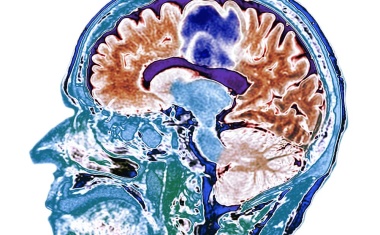

Quantensensoren: Hochpräzise Messungen im bewegten Gehirn

Was passiert bei einem epileptischen Anfall im Gehirn? Was nach einer Lähmung durch Schlaganfall? Was im Kopf von Parkinson-Erkrankten?